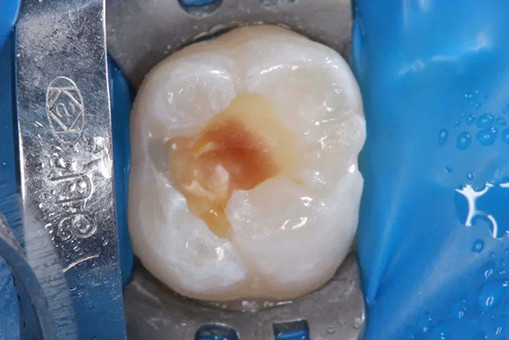

Лечение кариеса проводится следующим образом - сбор анамнеза, проведение местной анестезии, дентальный снимок (при необходимости), изоляция (коффердам), фотопротокол, удаление кариозных тканей (с использованием бора), антисептическая обработка полости, реставрация пломбировочным материалом, шлифовка, полировка.

До/после лечения